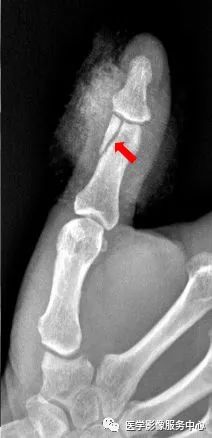

右手拇指远节指骨甲粗隆游离骨碎片影

右手拇指末节指骨见数条骨折线,骨折端对位对线尚可,右手拇指末节指骨粉碎性骨折。

右手拇指近节远端见斜行骨折透亮线,断端稍分离移位,右手拇指近节远端骨折。

右手中指远节近端背侧关节处见游离骨片影,右手中指远节骨折。